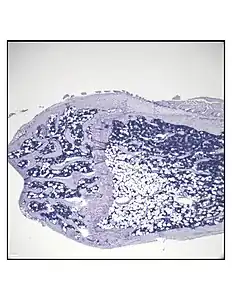

In order to understand the physiology of BMAT, various analytic methods have been applied. BMAds are difficult to isolate and quantify because they are interspersed with bony and hematopoietic elements. Until recently, qualitative measurements of BMAT have relied on bone histology,[51][52] which is subject to site selection bias and cannot adequately quantify the volume of fat in the marrow. Nevertheless, histological techniques and fixation make possible visualization of BMAT, quantification of BMAd size, and BMAT's association with the surrounding endosteum, milieu of cells, and secreted factors.[53][54][55]